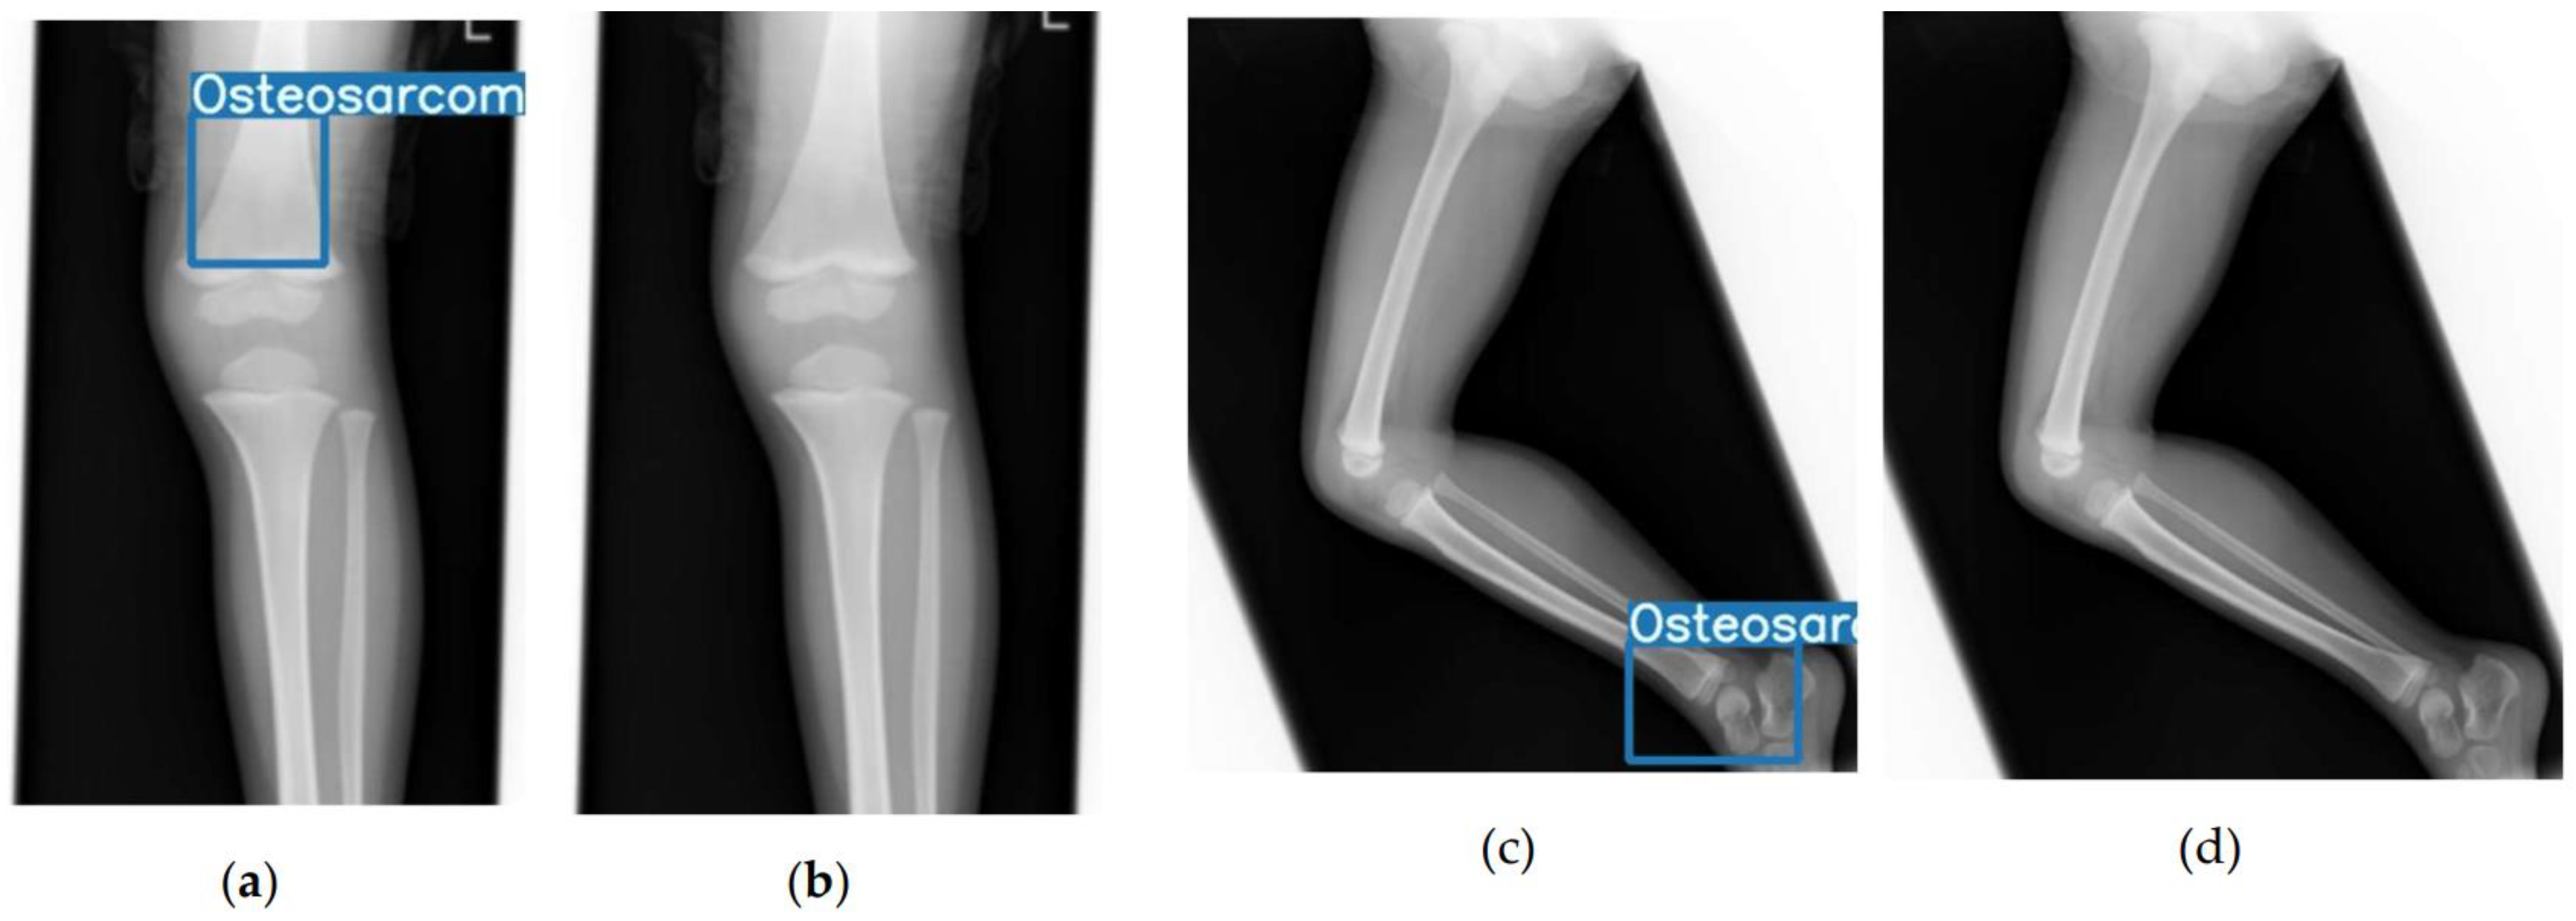

- Hasei, J.; Nakahara, R.; Otsuka, Y.; Nakamura, Y.; Hironari, T.; Kahara, N.; Miwa, S.; Ohshika, S.; Nishimura, S.; Ikuta, K.; et al. High-Quality Expert Annotations Enhance Artificial Intelligence Model Accuracy for Osteosarcoma X-Ray Diagnosis. Cancer Sci. 2024, 115, 3695–3704. [Google Scholar] [CrossRef]

- Hasei, J.; Nakahara, R.; Otsuka, Y.; Nakamura, Y.; Ikuta, K.; Osaki, S.; Hironari, T.; Miwa, S.; Ohshika, S.; Nishimura, S.; et al. The Three-Class Annotation Method Improves the AI Detection of Early-Stage Osteosarcoma on Plain Radiographs: A Novel Approach for Rare Cancer Diagnosis. Cancers 2024, 17, 29. [Google Scholar] [CrossRef]